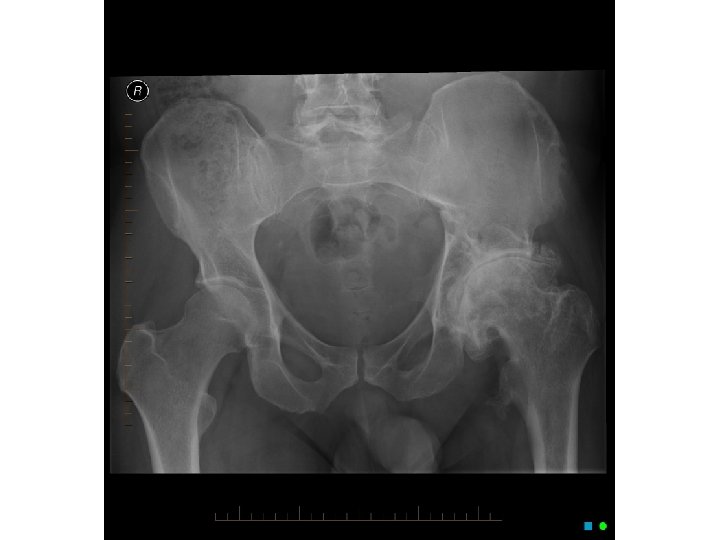

ANS: COMMINUTED FRACTURE • Comminuted fractures are those with 2 or more bone fragments are present • Sometimes difficult to appreciate on x-ray but will clearly show on CT scan • To fully describe the fracture, this is a closed R comminuted intertrochanteric fracture